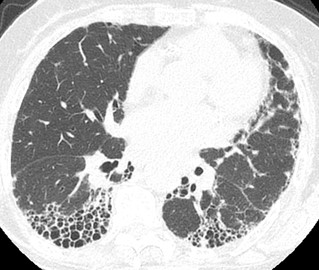

Figura 3 A e B: Paciente com artrite reumatóide e padrão de pneumonia intersticial usual. Note a franca progressão da fibrose no controle de 3 anos (B) com maior extensão do reticulado, das bronquiectasias e do faveolamento.

Em pacientes com FPI, a progressão radiológica geralmente se manifesta com aumento na extensão do padrão de pneumonia intersticial usual (PIU), tanto no plano axial como longitudinal, geralmente acompanhado do aumento no tamanho e quantidade de cistos de faveolamento. Além disso, o aumento na quantidade de bronquiectasias e bronquiolectasias de tração demonstrou ser um fator preditor de mortalidade na FPI(2). Em pacientes com outras doenças intersticiais pulmonares, o padrão de progressão pode ser variável, incluindo evolução das opacidades em vidro fosco para alteração reticulares ou evolução do reticulado para cistos de faveolamento, podendo se associar a aumento na extensão das bronquiectasias e bronquiolectasias de tração. Pacientes com padrão de pneumonia intersticial não específica (PINE) podem progredir para um padrão semelhante a PIU, por exemplo(3).